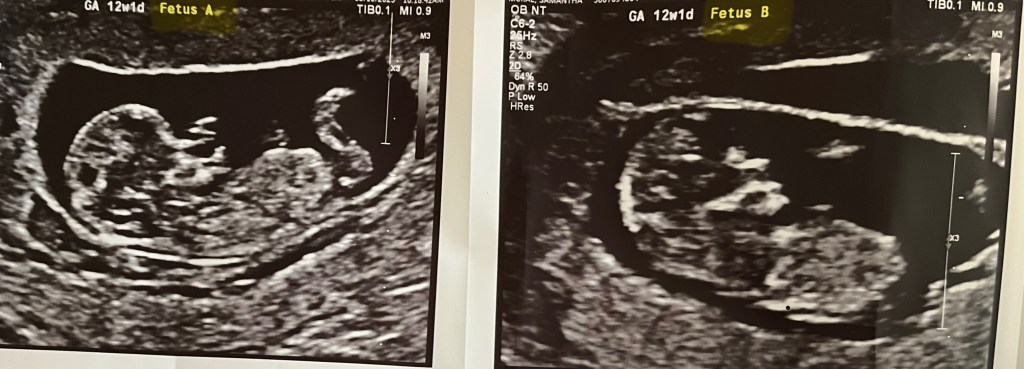

That’s right folks, we’re expecting, not one, but TWO new baby boy McRaes this Fall. It perhaps goes without saying, but twins were not on our family’s 2025 Bingo card and this has caused us to pause and re-assess what lies ahead for us and to continue discerning what the Lord is leading us into. Because the babies are due to arrive right around the time I had planned to start seminary full-time, that plan has begun to take on a new shape.